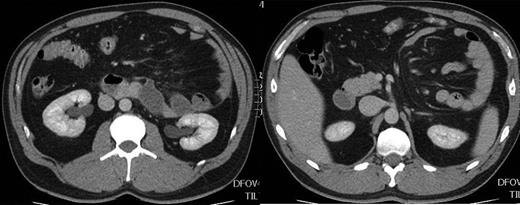

A 35-year-old male presented to accident and emergency with left upper abdominal pain, nausea and loss of appetite for 3 days. On retrospective questioning, he admitted to a propensity to vomit occasionally after large meals dating back to his childhood. On examination his abdomen was mildly distended with tenderness and a mass in his left upper quadrant. Chest and abdominal X-ray were normal. CT scan of the abdomen and pelvis with oral and i.v. contrast showed a left paraduodenal hernia (Fig. 1). Within 24 h his symptoms had resolved spontaneously and he was able to eat freely without pain and was discharged. He had mild left upper quadrant pain on a few occasions over the next 2 weeks and the option of surgical repair was discussed. As 50% or more paraduodenal hernias develop partial or complete small intestinal obstruction, surgical treatment was recommended. The patient decided to proceed to surgical treatment and a minimal access approach was planned.

CT scan of the abdomen demonstrating left paraduodenal hernia.